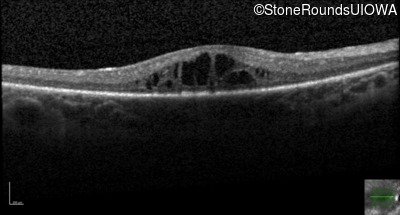

Optical Coherence Tomography - Right - 20/60 -1

Exemplar / OCT Stack